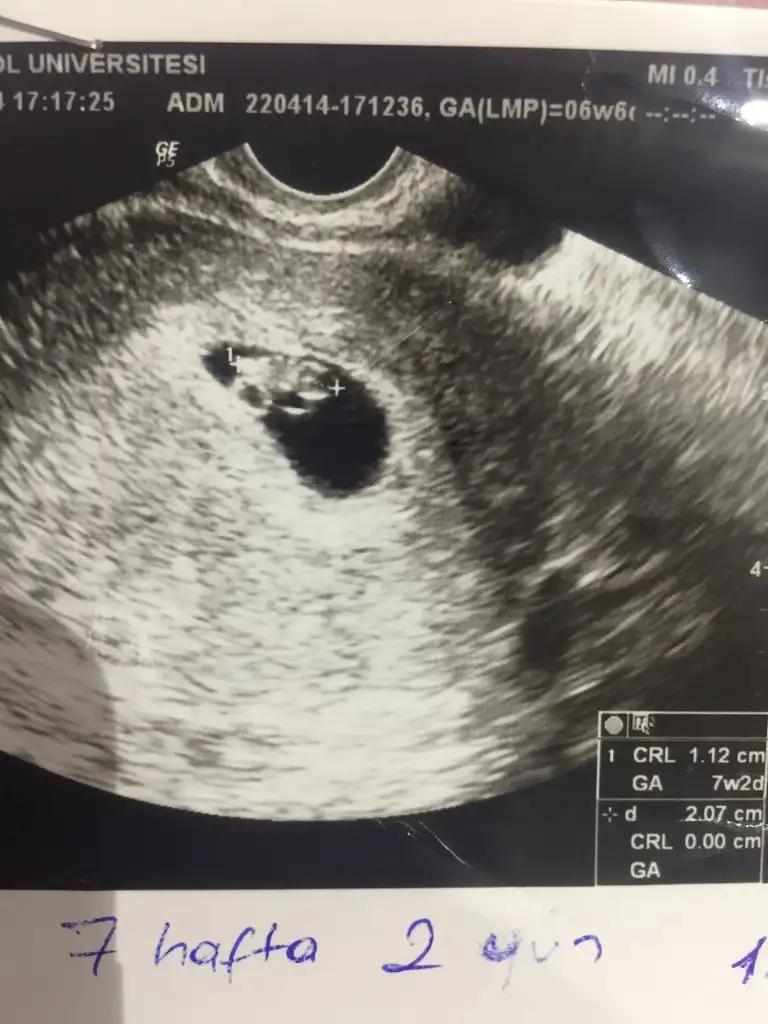

ilk fotoğraf benim kızımın abdominal usg 7+2

ikinci fotoğraf şu an ki gebeliğim yine abdominal 7+3

bir tahmininiz var mı acaba?